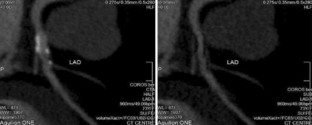

The challenge of coronary calcium on coronary computed tomographic angiography (CCTA) scans: effect on interpretation and possible solutions

Fig. 1

Fig. 2